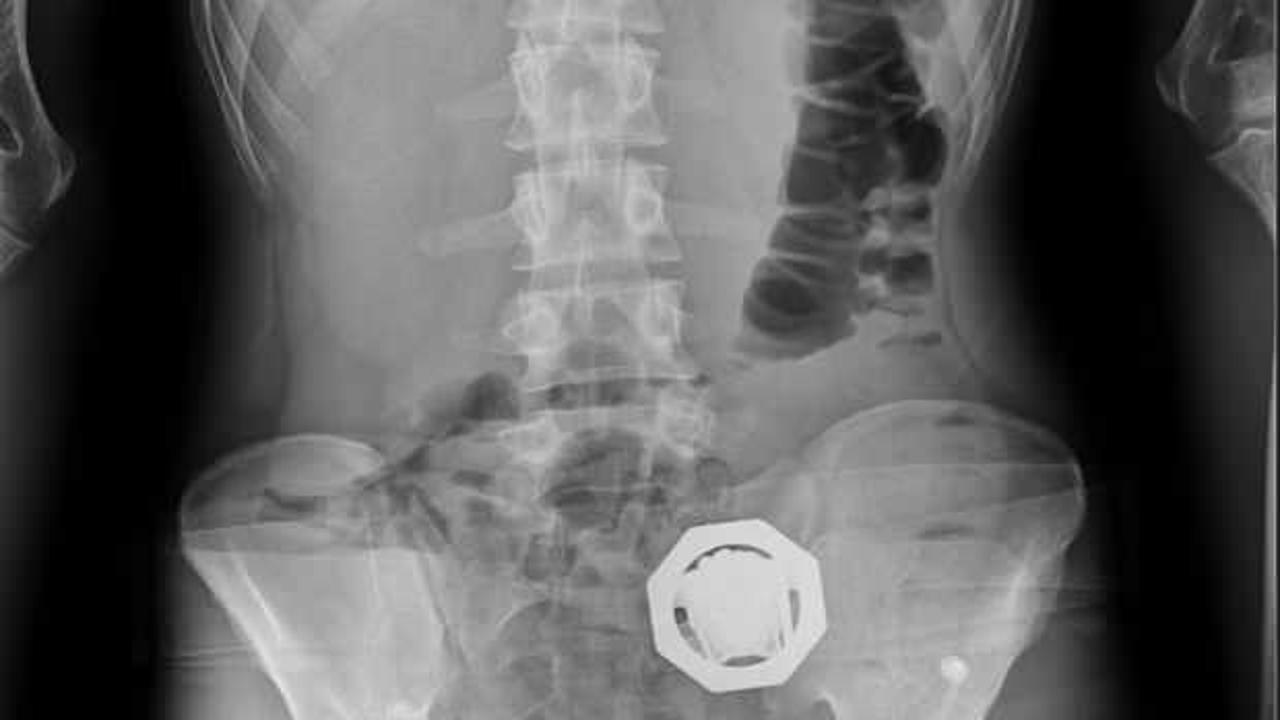

4 şüphelinin çekilen röntgenlerinde midelerinde 121 parça halinde 840 gram eroin tespit edildi. Uyuşturucular, yapılan tedavinin ardından çıkarıldı.